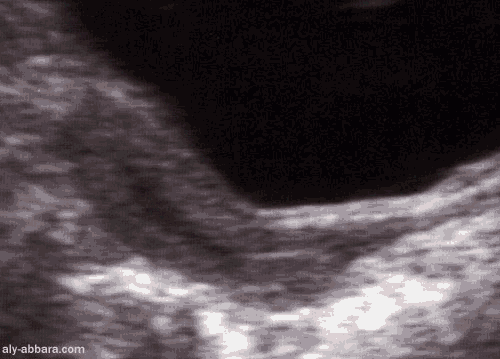

Aspect échographique de l'utérus avant la puberté